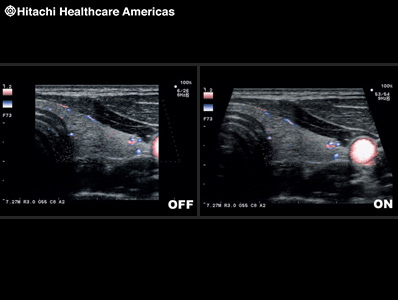

Displays blood flow with directional information at higher frame rates and spatial resolution compared to conventional methods. Detail and accuracy of blood flow information is greatly increased with reduced blooming of color.

Real-time side-by-side display of a B-mode image and Color Doppler image assisting in easy anatomical interpretation of blood flow.